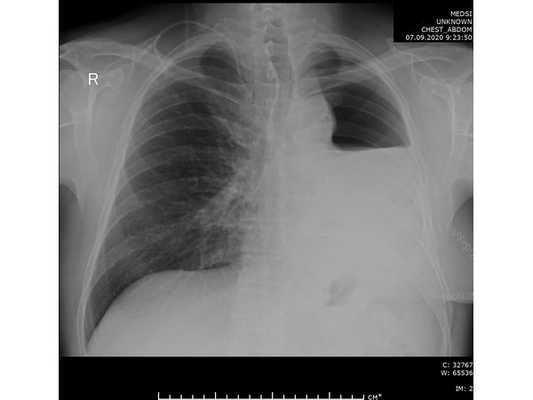

Проведена профилактическая стандартная антибактериальная терапия в течение пяти суток. По данным контрольной рентгенографии, отмечено смещение средостения в оперированную сторону.

- умеренно-дифференцированная аденокарцинома лёгкого (G2) с очаговой периневральной и лимфо-васкулярной инвазией (Pn1, LV1), выраженной фибропластической реакцией стромы, умеренной воспалительной инфильтрацией, фокусами некрозов.

- Размер опухоли — 6,0 х 4,5 х 3,5 см — pT2b.

- В 40 исследованных лимфатических узлах (4 группа — 5 шт., 5 группа — 4 шт., 7 группа — 10 шт., 9 группа — 1 шт., 10 группа — 2 шт., 11 группа и внутрилегочные — 18 шт.) метастазов опухоли не обнаружено — pN0.

- Края резекции без опухоли — R0.

- Область "подрастания" опухоли к адвентиции аорты и врастания опухоли в средостения была представлена фиброзной тканью с воспалительной инфильтрацией стромы.